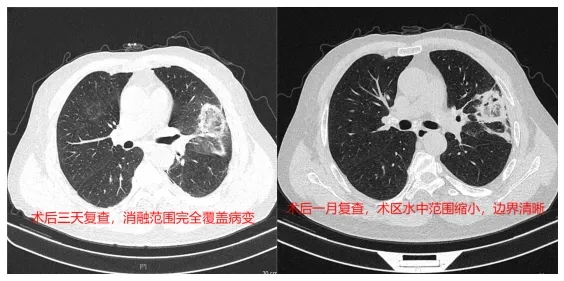

在CT引導(dǎo)下行

穿刺活檢術(shù)

+

微波消融治療術(shù)

經(jīng)過約30分鐘的努力

圓滿完成

且成功取材

(病理結(jié)果為腺癌)

術(shù)后

李大爺回病房

可以正常飲食

臥床休息6小時后

就能適當(dāng)下床活動

3天后復(fù)查CT

無并發(fā)癥出現(xiàn)

李大爺順利出院回家

1個月后復(fù)查

結(jié)節(jié)消融范圍理想

達(dá)到了預(yù)期效果